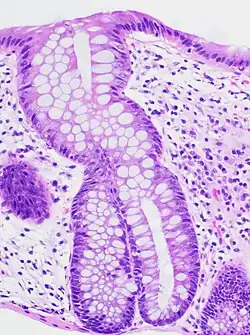

A micrograph demonstrating cryptitis, a microscopic correlate of colitis. H&E stain. | |

An important investigation in the assessment of colitis is biopsy for histopathology. A very small piece of tissue (usually about 2mm) is removed from the bowel mucosa during endoscopy and examined under the microscope by a histopathologist. A biopsy report generally does not state the diagnosis, but should state any presence of chronic colitis, give an indication of disease activity, as well as state the presence of any epithelial damage (erosions and ulcerations).[6]

Histopathology findings generally associated with chronic colitis include:[6]

- Crypt degeneration

- Crypt branching and other architectural distortions

- Paneth cell (pictured) or gastric metaplasia (only applies in the left colon and rectum)

Other findings include basal plasmacytosis and mucin depletion.[6] Histopathology findings generally associated with active colitis include:[6]

- Neutrophilic cryptitis (neutrophils within crypt epithelium)

- Crypt abscesses (luminal neutrophilic aggregates)

- Gland destruction

- Ulceration (seen here as absence of epithelium, and granulation tissue with many fibroblasts)